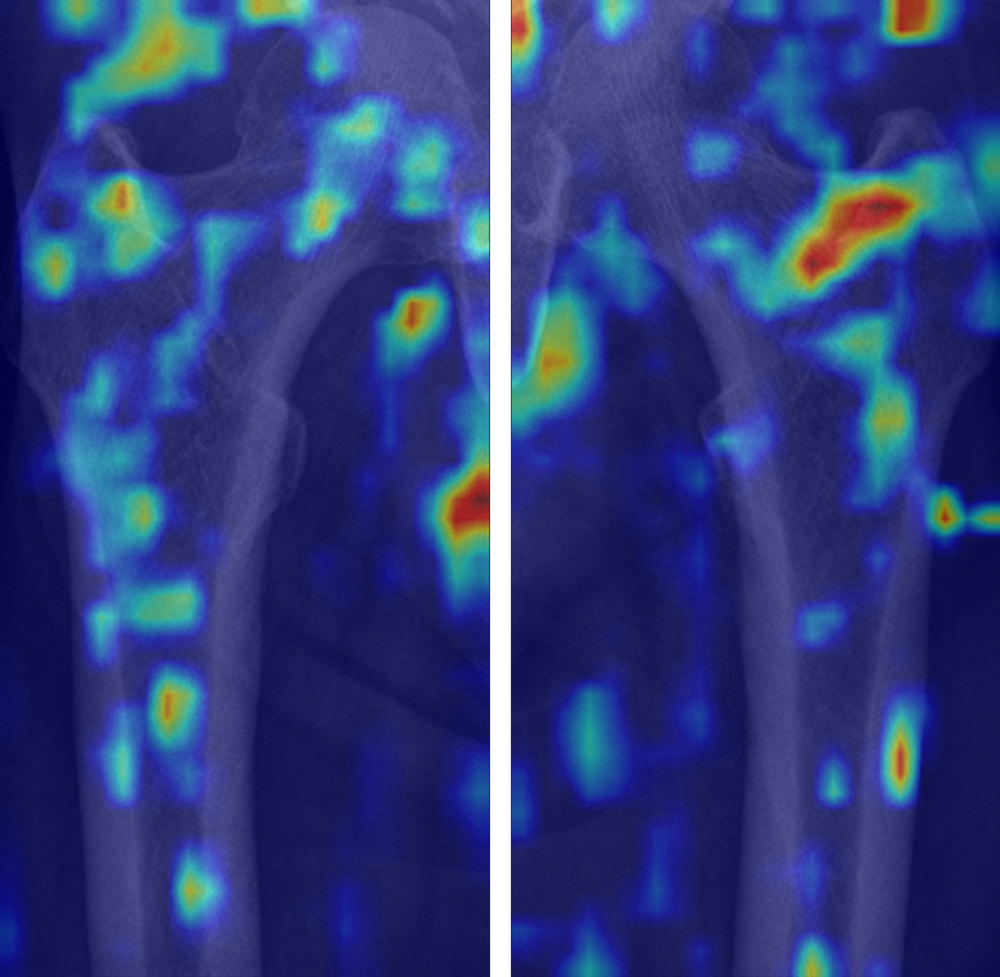

Figure 7. Gradient-weighted class activation mapping (Grad-CAM) images of true-negative cases for diagnosis of osteoporosis. True-negative cases dominantly demonstrated scattered color distribution on the trabecula of proximal femur. We used the jet colormap scale, where the red color stands for high relevance, yellow for medium relevance, and blue for low relevance.

High-res (TIF) version